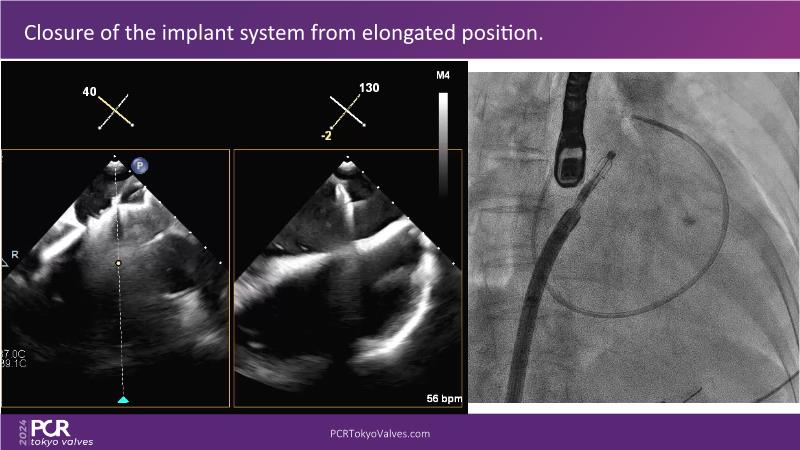

Watch this session to get an overview of a new TEER device, follow the step-by-step procedure related to initial experiences with this device for a Japanese patient with degenerative mitral regurgitation, learn about the latest data from RCT and registries, and follow discussions of challenging TEER cases!

- To learn procedural step-by-step of novel device